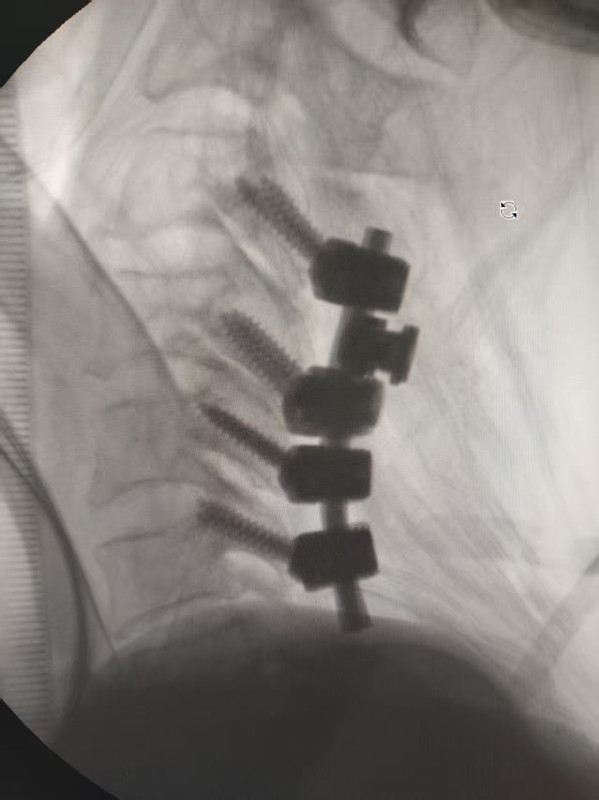

患者术中透视钉棒固定情况

手术当日,荆珏华教授带领医院骨科团队全力攻坚。手术过程中,他始终以“传、帮、带、教”为己任,全程同步细致讲解关键操作要点:从骨折复位的精准定位技巧,到脊髓减压的安全保护要点,再到内固定植入的精准操作规范,每一个核心环节都毫无保留、倾囊相授。医院潘宏、邱新建主任医师和余正友、夏西尚副主任医师等年轻医师在旁全程观摩学习,通过“实战带教”的沉浸式学习,直观掌握了脊柱复杂手术的核心技术与风险防控要点。整个手术历时3个半小时,在荆教授的精准操控和脊柱外科、麻醉科团队的默契配合下,成功完成颈椎后路颈3-6椎体侧块螺钉固定及全椎板减压等一系列复杂操作,术后患者生命体征平稳,四肢感觉及肌力已初步恢复。